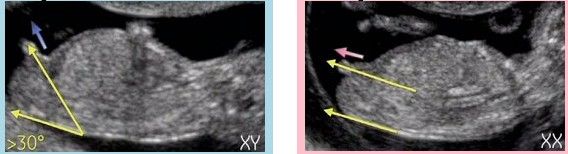

怀孕12周的时候,孕妈的B超图上会有宝宝身体侧面的照片,有的照片上,宝宝的屁屁位置会有一个尖尖的小尾巴,男宝女宝都会有,那个尖尖的东西叫“生殖结节”。有的照片照到了生殖结节,有的照片没有照到,而能用NUB理论辨别性别的是照到生殖结节的宝宝。

上图显示,生殖结节向上翘起30度以上的是男宝,翘起不明显的是女宝。

以前看DISCOVERY的《子宫内日记》,里边也说到医生是通过生殖结节角度辨别性别,所以这个方法是相对比较靠谱的,但准确率只有75%-90%,可以参考但不能迷信。